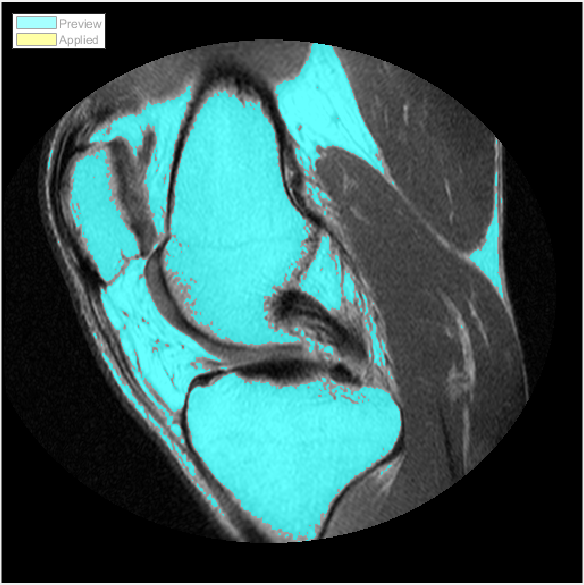

Следующий рисунок показывает результаты использования Ручной пороговой обработки.

Изображение колена не имеет четко определенных различий в интенсивности пикселей между передним планом и фоном, и пороговая обработка не походит на лучший выбор сегментировать это изображение.